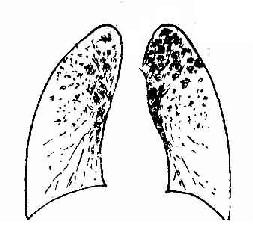

2)肺粟粒性結核病:又稱血行播散型肺結核病。急性粟粒性肺結核病常是全身粟粒性結核病的一部分。偶爾,病變也可僅局限於兩側肺內。這是由於支氣管周圍肺門或縱隔淋巴結乾酪樣壞死破入附近的靜脈(如無名靜脈、頸內靜脈、上腔靜脈),含大量結核菌的液化物經右心和肺動脈播散至雙肺所引起。肉眼觀,雙肺充血,重量增加,切面暗紅,密布灰白或灰黃色粟粒大小的結節,微隆起於切面,並顯露於肺膜表面。慢性粟粒性肺結核病多見於成年人,這時肺原發綜合徵業已鈣化痊癒,結核桿菌由肺外(骨關節、泌尿生殖道及腎上腺等處)結核病灶較長期、間歇性地進入血流,播散於肺內,形成新舊不等的病變。間隔時間可為數月甚至數年。患者多因結核性腦膜炎死亡。